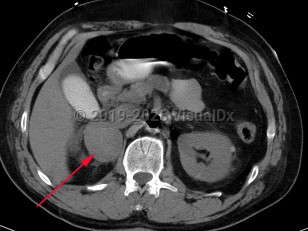

Pheochromocytoma (PCC) is a rare catecholamine-secreting neoplasm of adrenal origin; when it is extra-adrenal, it is referred to as paraganglioma. PCC is known as the "great masquerader" because of its similarity in clinical presentation to many other conditions. Up to 15% of patients may be asymptomatic. The most common presenting symptoms are hypertension (including labile hypertension), palpitations, increased sweating, severe headache, tremors, pallor, and dyspnea. Atypical symptoms include anxiety, abdominal pain, nausea, vomiting, constipation, insomnia, and weight loss. The prevalence of PCC in patients with hypertension is less than 0.2%. Rarely, paragangliomas may occur in the heart. Cardiovascular complications of catecholamine excess are rare but can lead to stress cardiomyopathy. Clinical presentation is characterized by transient duration of symptoms (eg, 15-20 minutes) that may recur several times a day. Physical exertion (moderate to extreme exercise) or bowel movements may provoke symptoms. Sometimes a pheochromocytoma is found incidentally during a workup.

The majority of PCCs are intra-adrenal and solitary. Approximately 10% of all catecholamine-secreting tumors will be malignant. PCC may occur at any age but has the highest prevalence in individuals aged 20-50 years.